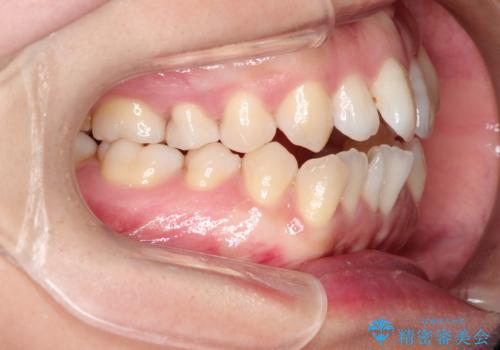

前歯がガタガタで咬めない ワイヤーによる抜歯矯正で整った歯並びへ

- 前歯がガタガタなのと、前歯でものが噛めないことを主訴に来院されました。

前歯の叢生があり、上下の前歯が接触していない開咬という状態でした。

左側の上下の前から4番目の歯を抜歯して、矯正することとしました。

ガタガタがなくなり、上下の前歯が接触すようになり、見た目とともに咬みやすくすることができました。